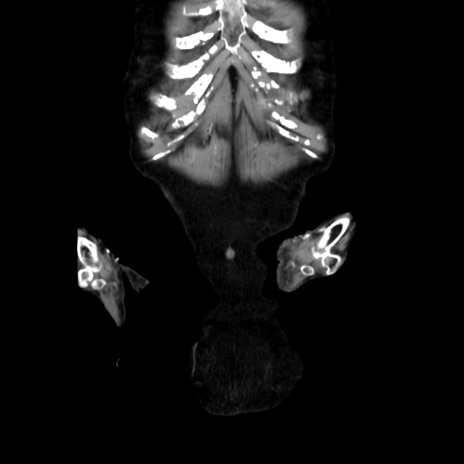

他院CT

横断像